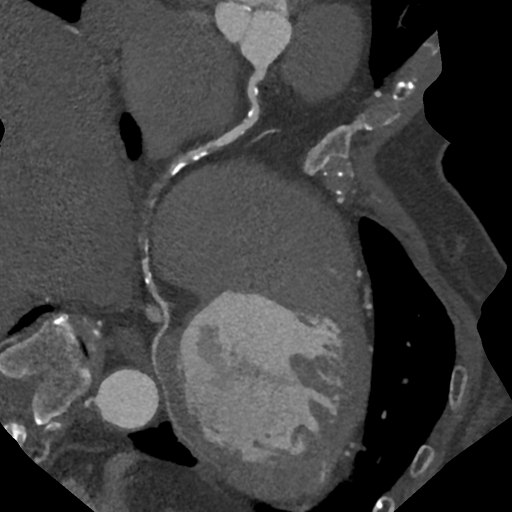

PCI前の冠動脈評価CT

CTでは、心臓に酸素や栄養を送る冠動脈と呼ばれる血管の状態(狭窄や閉塞)や、心臓の全体像を知ることができます。また、バイパスなど手術後の経過なども調べることができます。